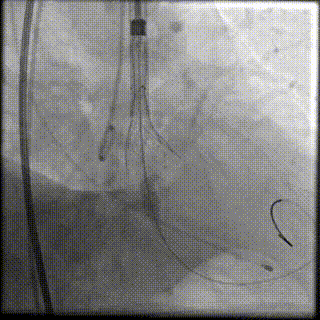

主动脉根部造影

22mm球囊预扩

输送器顺利过弓跨瓣

瓣环零位定位释放

第一次释放到工作位

工作位造影位置偏深

完全回收再次定位

第二次释放到工作位,位置理想

瓣膜完全释放

瓣膜完全释放后造影

外周造影